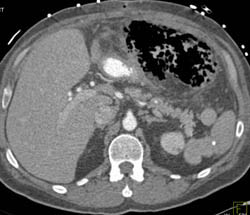

Desmoid Tumor Simulates A Gastric Tumor